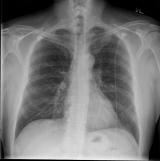

ChestLink成为首个在欧盟获批的自主医疗成像人工智能工具